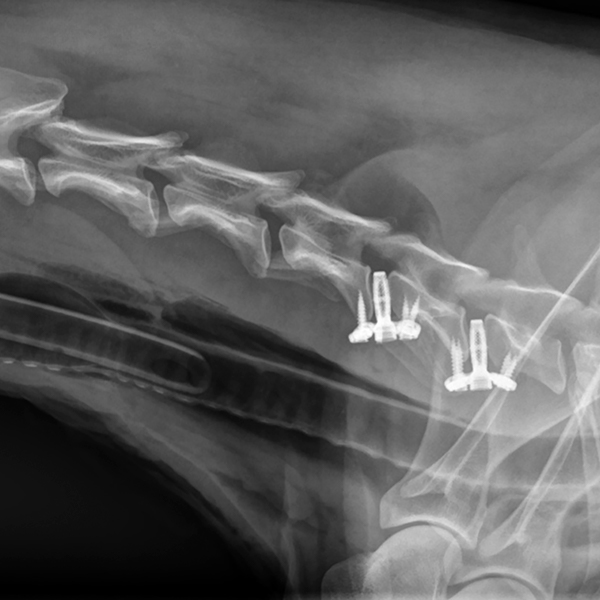

C-LOX ist ein Bandscheibenersatz-Implantat für die Halswirbelsäule von Hunden. Dieser intervertebral verankerte Fusions-Spacer kann zur Behandlung der caninen zervikalen Spondylomyelopathie (Wobbler-Syndrom) eingesetzt werden und bietet eine wertvolle Alternative zu komplexeren Distraktions-Fusions-Techniken. C-LOX wurde von RITA LEIBINGER in Zusammenarbeit mit Prof. Dr. Frank Forterre der Universität Bern (Schweiz) entwickelt.

C-LOX ist ein Distraktions-Fixationssystem, das zwei Wirbelkörper distrahiert, um Druck vom Rückenmark zu nehmen. Es kombiniert die Vorteile eines intervertebralen Spacers, einer rigiden Titanplatte und einer winkelstabilen Schraubenfixation. Die C-LOX Cages erhalten nicht nur das natürliche anatomische Profil der Wirbelsäule, sondern bieten auch sehr hohe Stabilität sowie komfortable Platzierung und Fixation.

Die Dodekaeder-Struktur des Cages bietet eine größere Oberfläche für das Knochenwachstum. Das verbessert Osseointegration und zelluläre Anhaftung, fördert somit die Knochenneubildung und reduziert Implantatversagensraten.